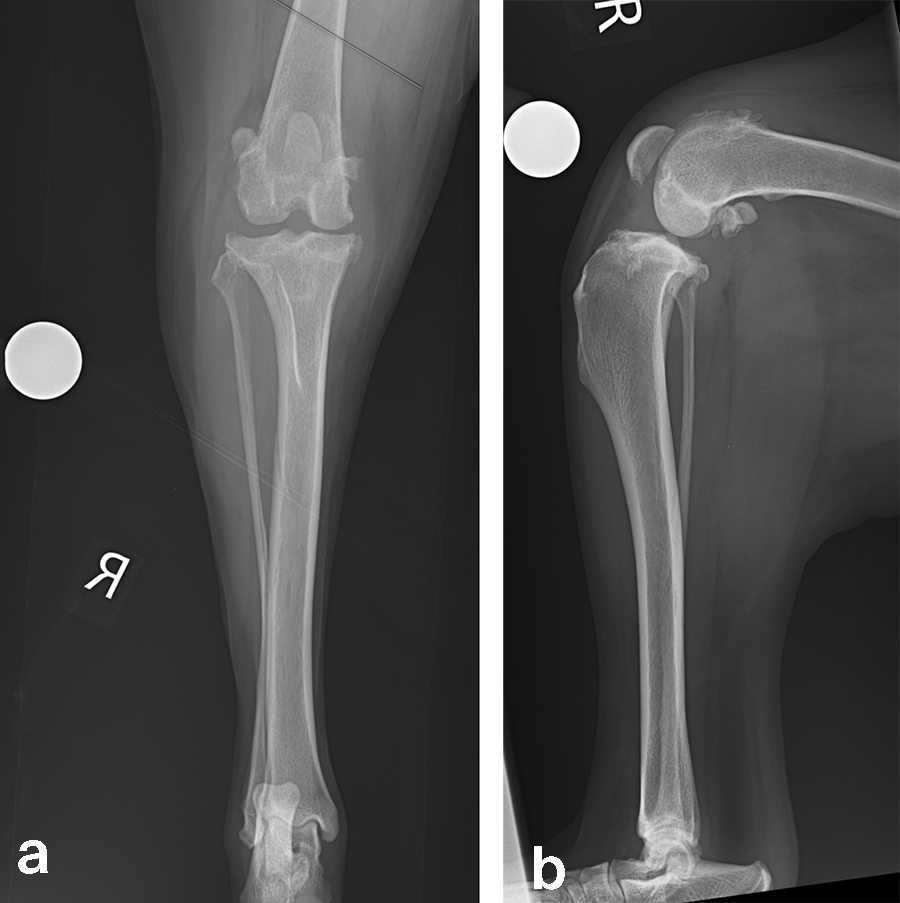

Case 2: Rosie, 3‐year‐old black Labrador Retriever, 23.3 kg

(Case provided by William B Saunders, Texas, USA)

A 23.3 kg 3-year-old spayed female black Labrador Retriever presented with a history of chronic, progressive left pelvic limb lameness. Her clinical examination was suggestive of left cranial cruciate ligament (CCL) rupture. Medical and surgical treatment options were discussed with the clients. They elected to have Rosie’s knee treated with arthroscopy and TPLO.

Left stifle arthroscopy was performed and a partial CCL rupture with incompetent remand was identified. The remaining CCL was debrided with a motorized shaver. The meniscus was healthy/non-injured based on visual inspection and probing. Arthroscopy portals were closed, and exposure of the proximomedial tibia was performed.

Based on preoperative templating, a 21 mm radial saw blade was used to perform an osteotomy of the proximal tibia. The plateau was leveled to a final target slope of 5° and the osteotomy was stabilized with a 3.5 mm ARC TPLO plate.